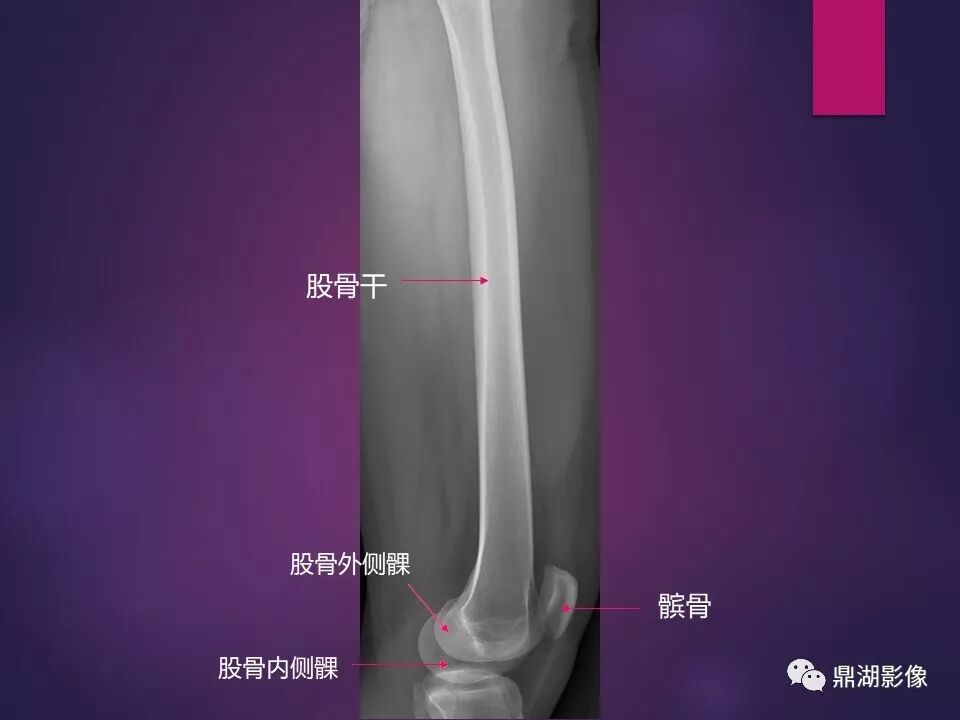

来源于:鼎湖影像 贵阳医学院医学影像系